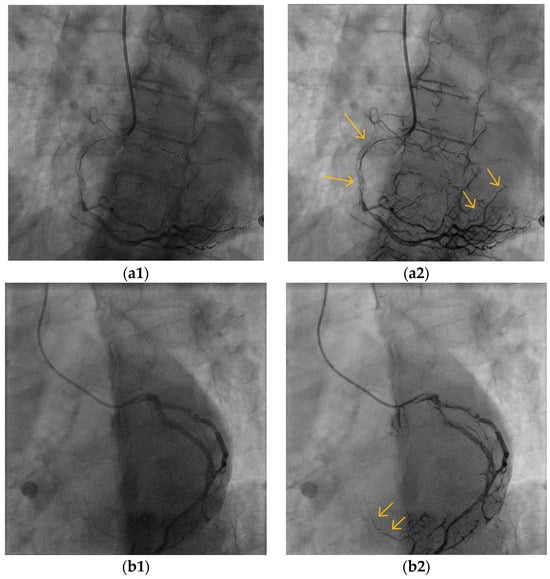

5.2. Blood Vessel Interiors

5.3. Small Blood Vessels

5.4. Low-Contrast Agent, Low-Radiation, and No Contrast Agent